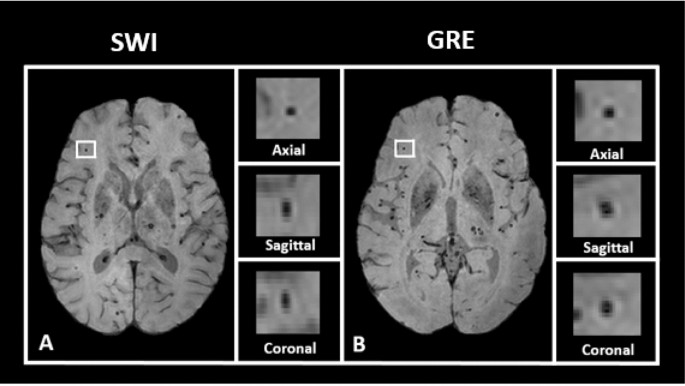

Automated Detection Of Cerebral Microbleeds On T2 Weighted Mri Scientific Reports